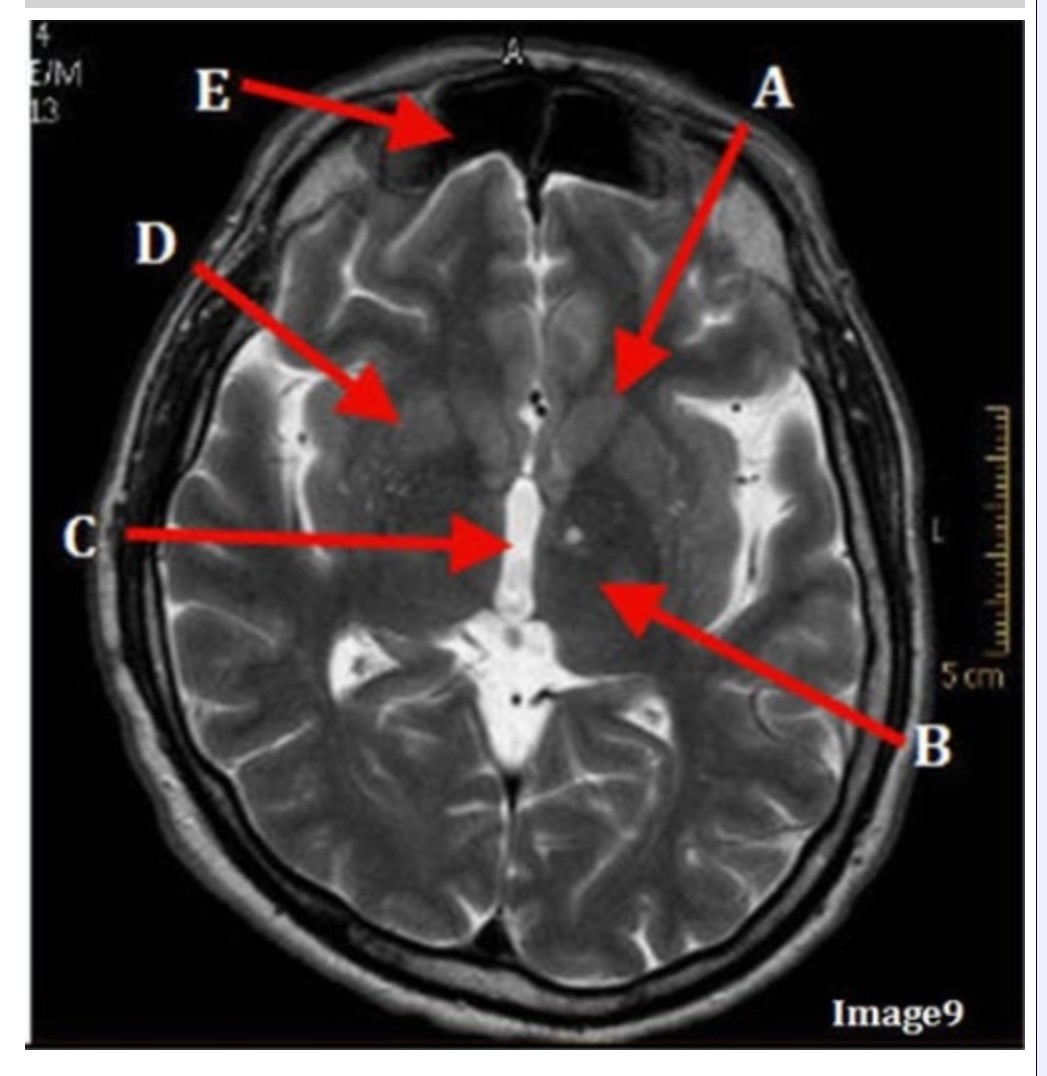

Letter C in Image 9 is pointing to:

A. Third ventricle

B. Thalamus

C. Lentiform nucleus

D. Caudate nucleus

Letter B in Image 9 is pointing to:

A. Third ventricle

B. Thalamus

C. Lentiform nucleus

D. Caudate nucleus

Letter D in Image 9 is pointing to:

A. Third ventricle

B. Thalamus

C. Lentiform nucleus

D. Caudate nucleus

Letter E in Image 9 is pointing to:

A. Maxillary sinus

B. Sphenoid sinus

C. Frontal sinus

D. Ethmoid sinus

Letter A in Image 9 is pointing to:

A. Third ventricle

B. Thalamus

C. Lentiform nucleus

D. Caudate nucleus

Image 9 is an example of a _____ weighted sequence acquired in the _______ scan plane.

A. T1; Axial

B. T2 FLAIR; Sagittal

C. T2; Axial

D. T2; Coronal